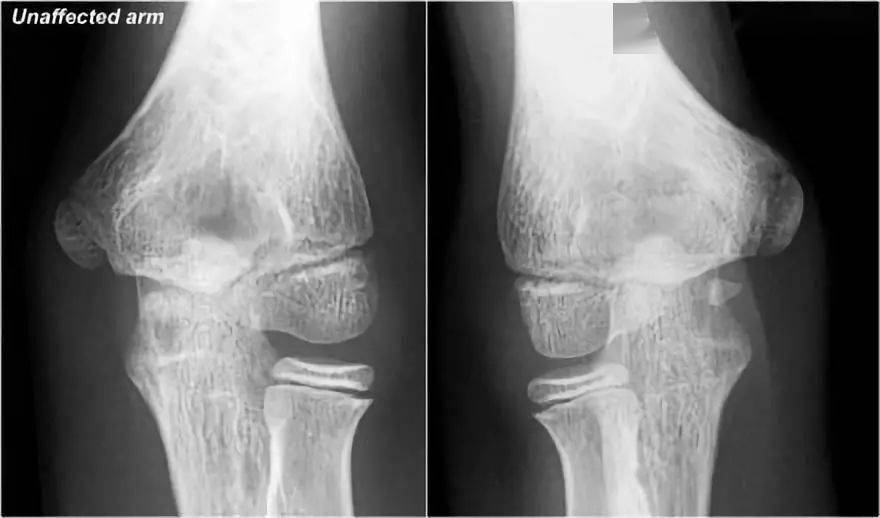

little leaguer的肘部也被称为内侧性上睑下垂,有些人称之为骨骺溶解.